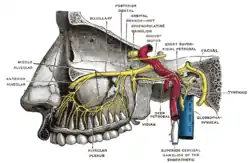

Alveolar branches of superior maxillary nerve and sphenopalatine ganglion. | |

Plan of the facial and intermediate nerves and their communication with other nerves. | |